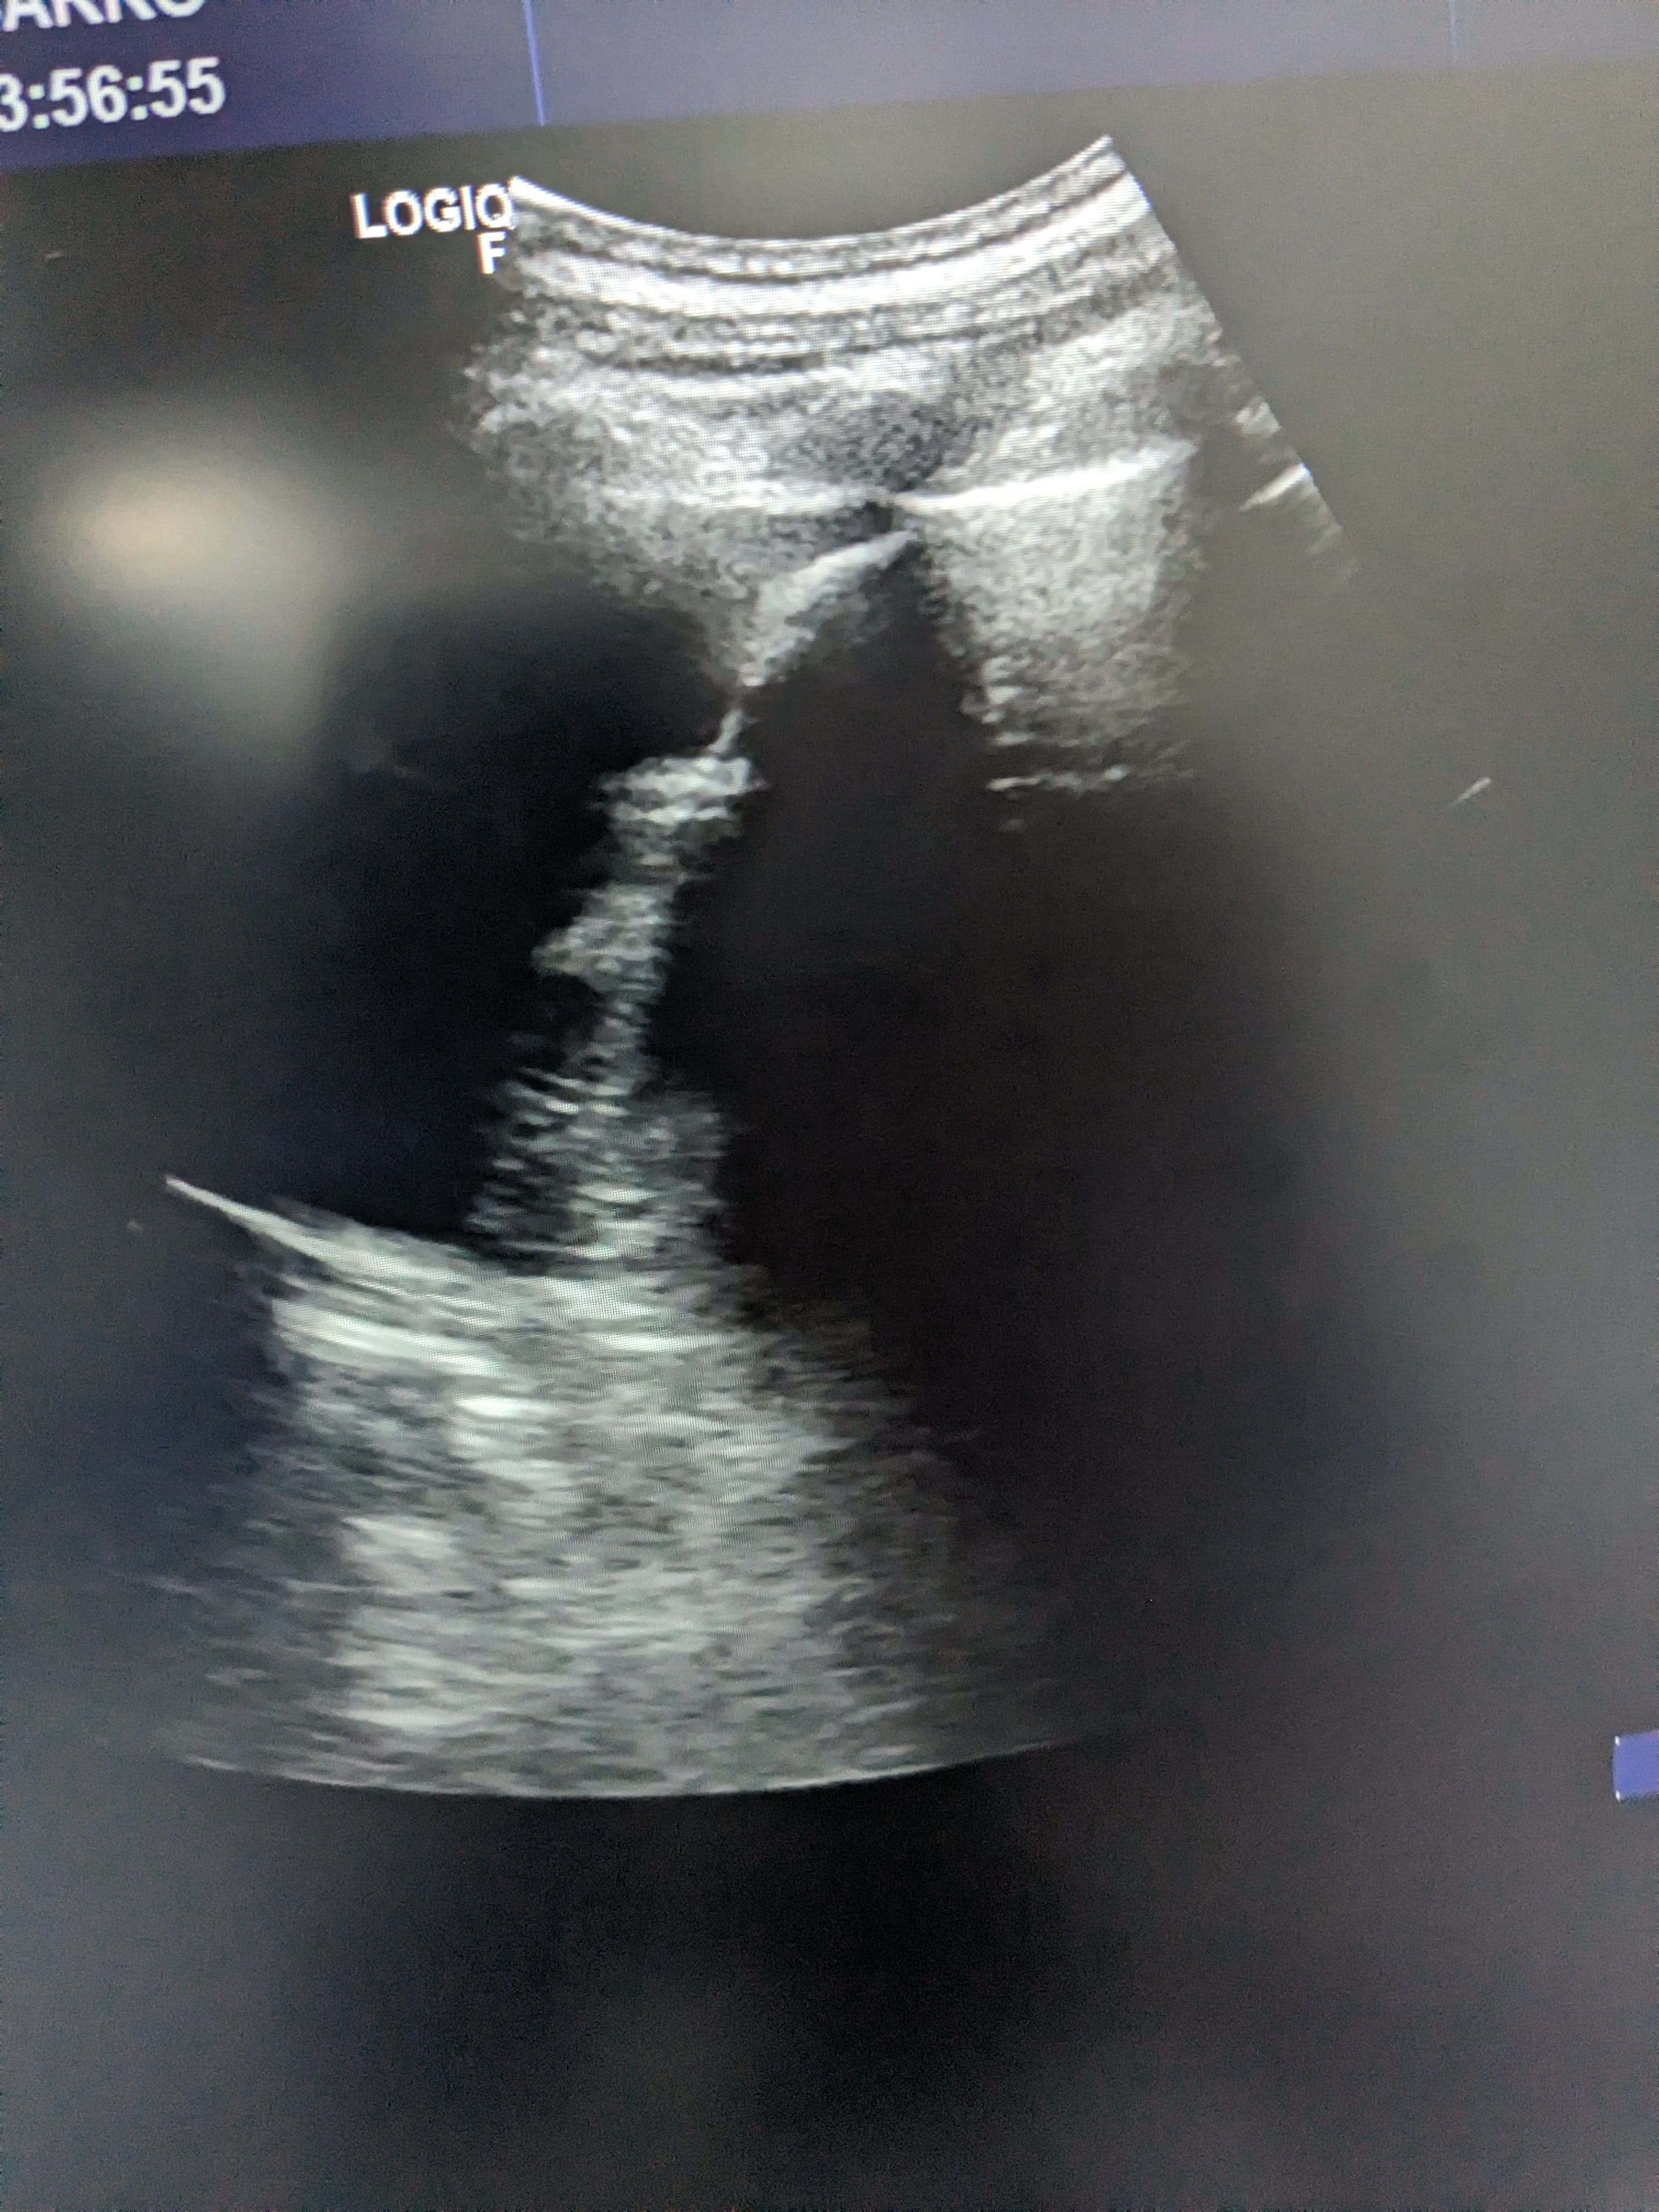

Se hace ecografía clinica en la consulta de atención primaria, observamos derrame pleural en pulmón izquierdo hasta medio campo pulmonar.